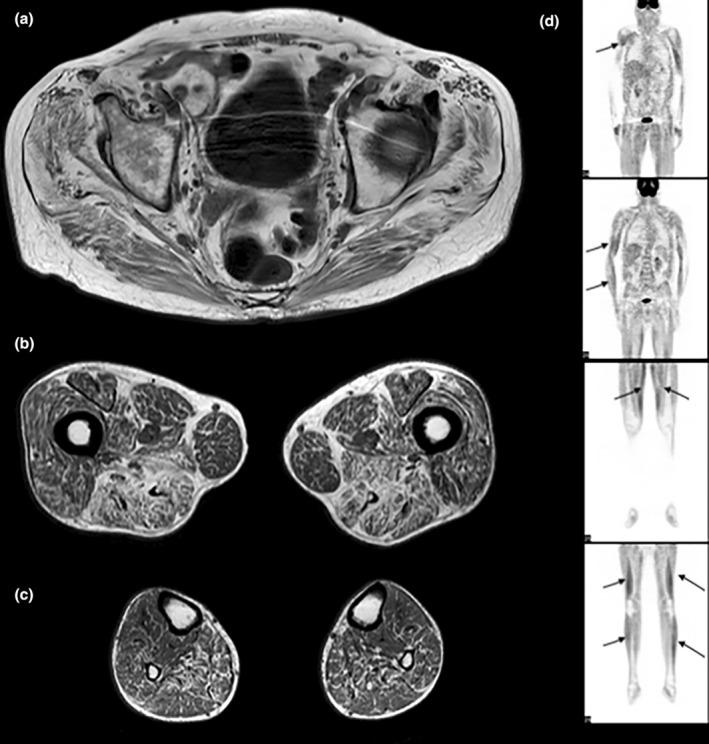

The patients, aged 37, 46, and 56 years, presented progressive weakness with subacute worsening and stiffness, in the context of severe weight loss. The weakness mainly involved the proximal limbs and axial muscles. Creatine kinase levels were 1400-2900 IU/L and electromyography revealed a myopathic pattern with spontaneous complex repetitive discharges. Muscle biopsies showed vacuoles containing glycogen and autophagic material along with the presence of sarcolemmal complement membrane attack complex deposits. There was no evidence of a genetic glycogen metabolic disorder. IgGκ monoclonal gammopathy was identified in all cases, without signs of lymphoplasmocytic proliferation. All patients improved with a treatment combining corticosteroids, intravenous immunoglobulins, and immunosuppressants, and two patients recovered walking ability.

We report a new muscle disease defined by a vacuolar myopathy characterized by axial and proximal muscle weakness with prominent stiffness and high frequency discharges on electromyography associated with monoclonal gammopathy, defined under the acronym VAMMGAS.